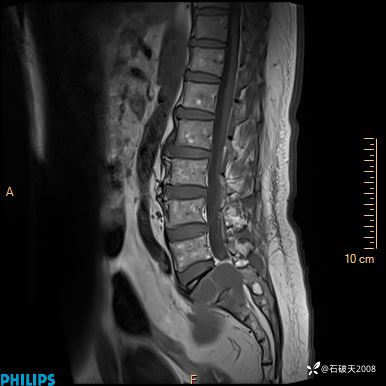

2023年3月份MRI影像

T2矢状位